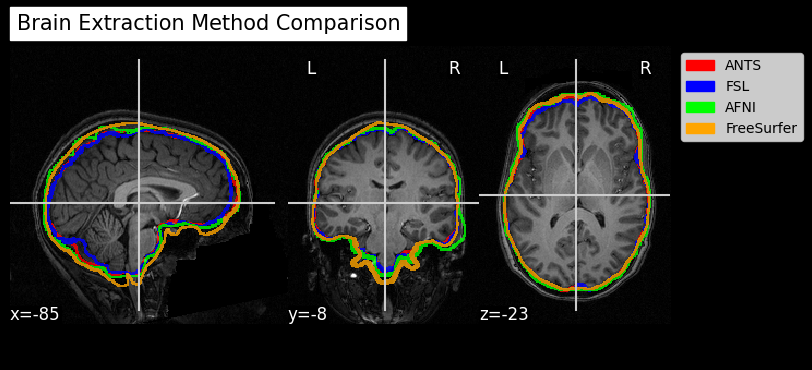

Since fMRI studies focus on brain tissue, our first step is to remove the skull and non-brain areas from the image.

In order to analyze fMRI data, you will need to load an fMRI analysis package. In this example we will use the following packages and algorithms to skull-strip the anatomical image:

Advanced Normalization Tools (ANTs): antsBrainExtraction.sh

Analysis of Functional NeuroImages (AFNI): 3dSkullStrip

FreeSurfer: SynthStrip

FSL (FMRIB Software Library, created by the University of Oxford): BET - Brain Extraction Tool